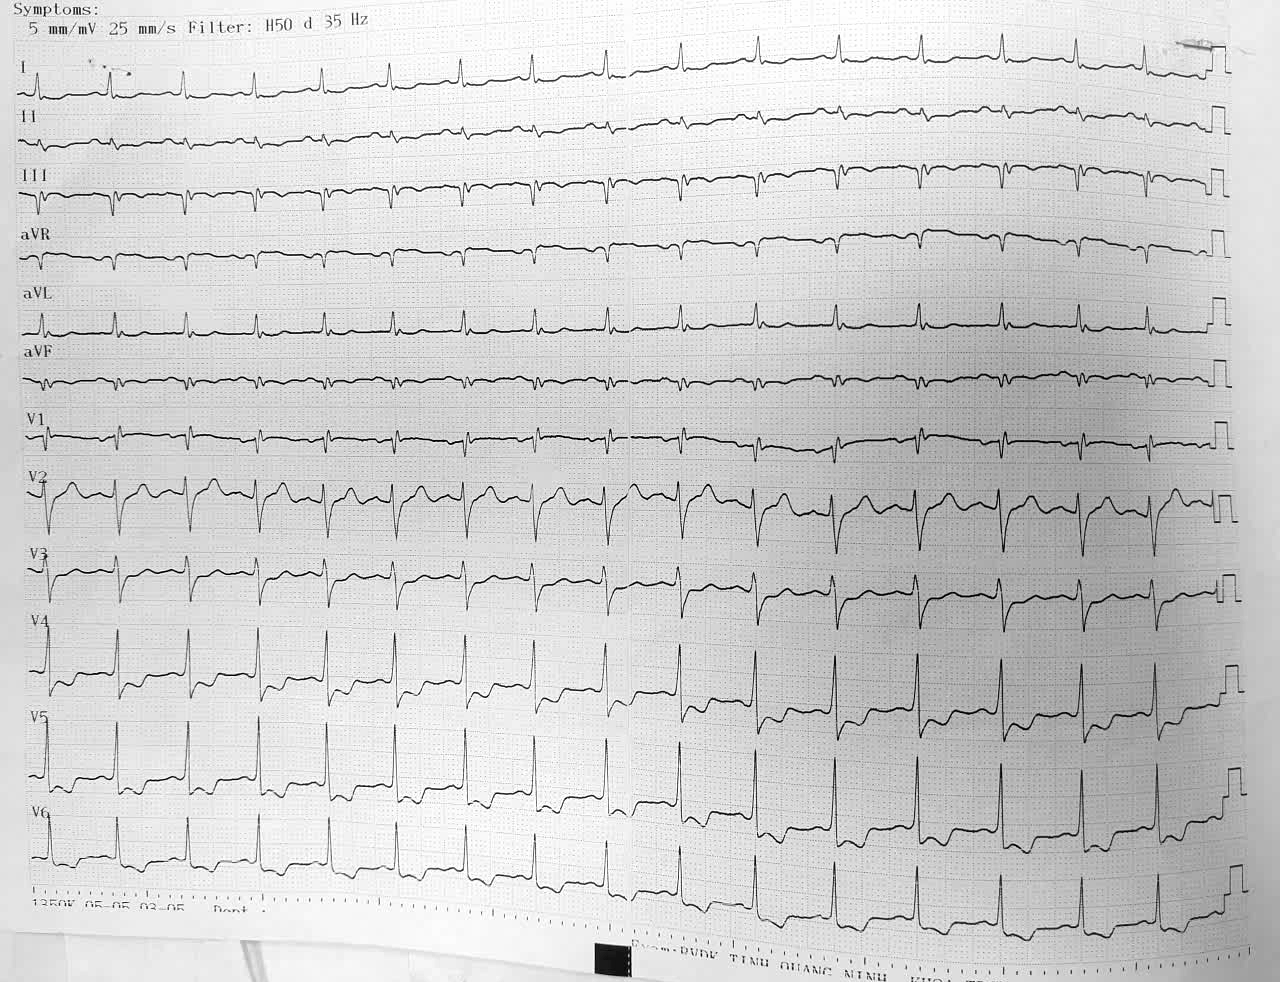

Điện tim bệnh nhân Q. trước mổ bình thường.

Vài giờ sau mổ, bệnh nhân bất ngờ xuất hiện đau ngực trái lan ra vai và cánh tay, kèm vã mồ hôi, khó thở. Nhận thấy bệnh nhân có diễn biến bất thường, các bác sĩ nhanh chóng hội chẩn chuyên khoa Tim mạch, kết quả điện tâm đồ cho thấy bệnh nhân nhồi máu cơ tim cấp thành dưới sau mổ nội soi cắt túi mật - Loét hành tá tràng đang liền sẹo.

Nhịp tim bất thường trên điện tâm đồ của bệnh nhân Q. sau phẫu thuật.